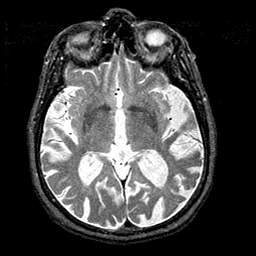

Alzheimer's disease MR T2-weighted -- Slice #23

[Home][Help][Clinical][Tour 1][Tour 2] Slice 23